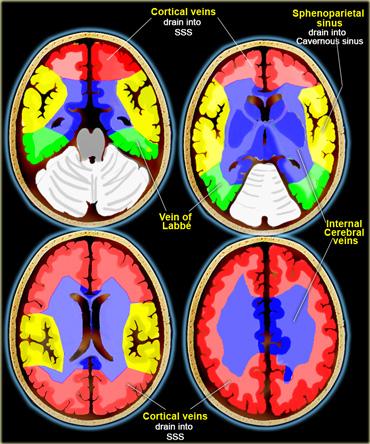

Vùng tưới máu tĩnh mạch não

Có sự biến đổi rất lớn trong các vùng dẫn lưu tĩnh mạch.

Các hình minh họa bên trái chỉ nên được xem như một hướng dẫn tham khảo sơ bộ.